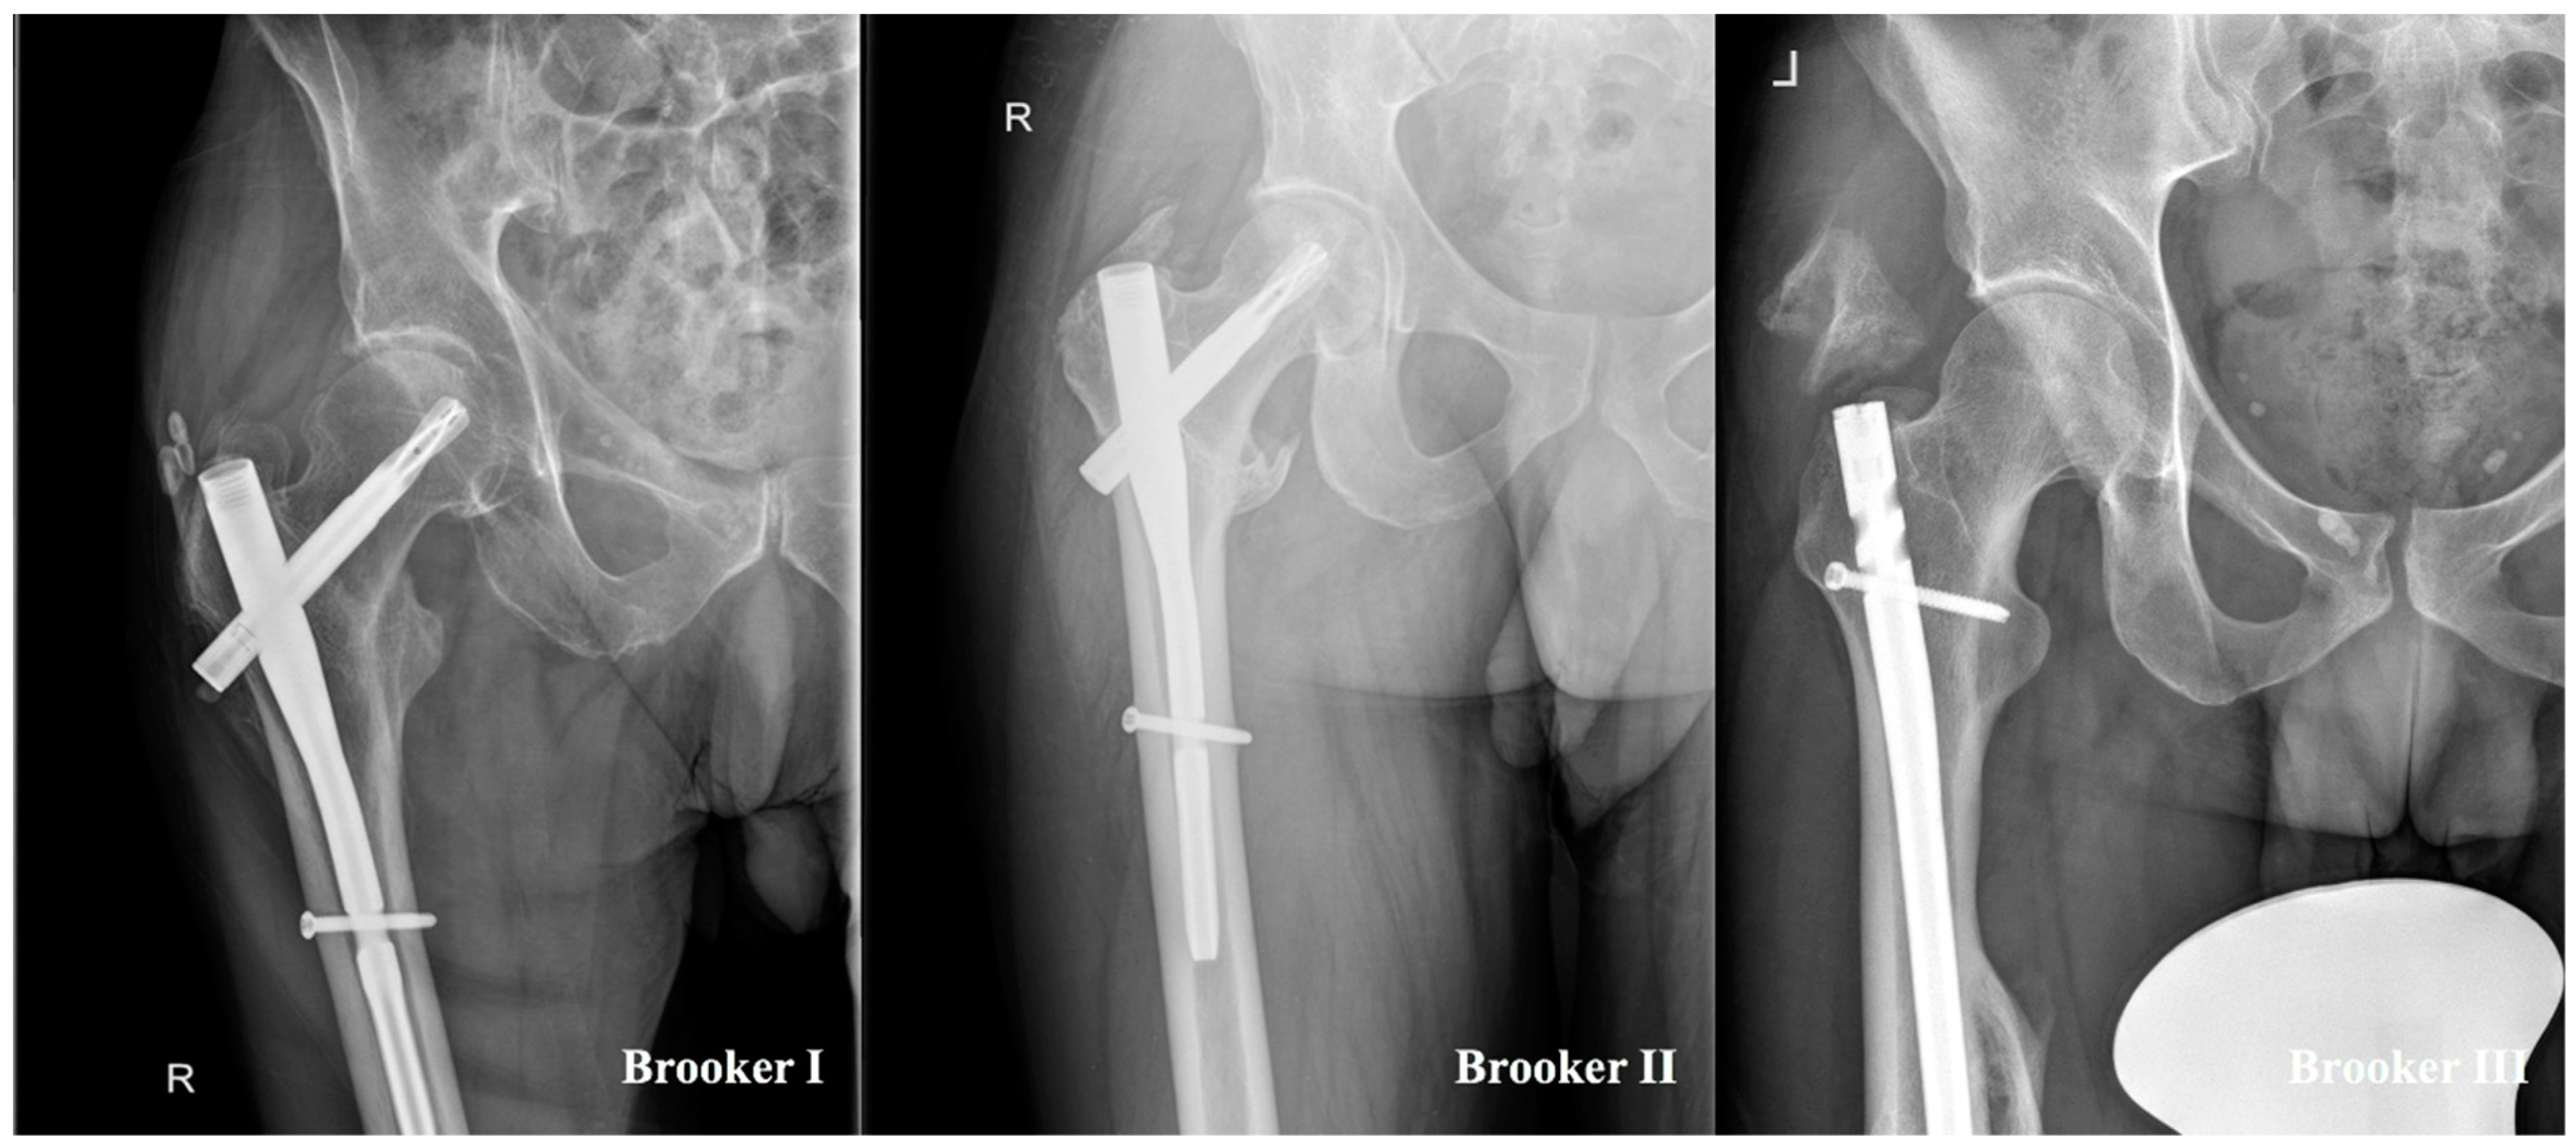

- Brooker, A.F.; Bowerman, J.W.; Robinson, R.A.; Riley, L.H.J. Ectopic ossification following total hip replacement. Incidence and a method of classification. J. Bone Jt. Surg. Am. 1973, 55, 1629–1632. [Google Scholar] [CrossRef]

- Hug, K.T.; Alton, T.B.; Gee, A.O. Classifications in brief: Brooker classification of heterotopic ossification after total hip arthroplasty. Clin. Orthop. Relat. Res. 2015, 473, 2154–2157. [Google Scholar] [CrossRef]

| Brooker | |||

| I, n (%) | 4 (44.4) | 3 (60.0) | |

| II, n (%) | 4 (44.4) | 2 (40.0) | |

| III, n (%) | 1 (11.1) | 0 (0.0) | |

| IV, n (%) | 0 (0.0) | 0 (0.0) | |